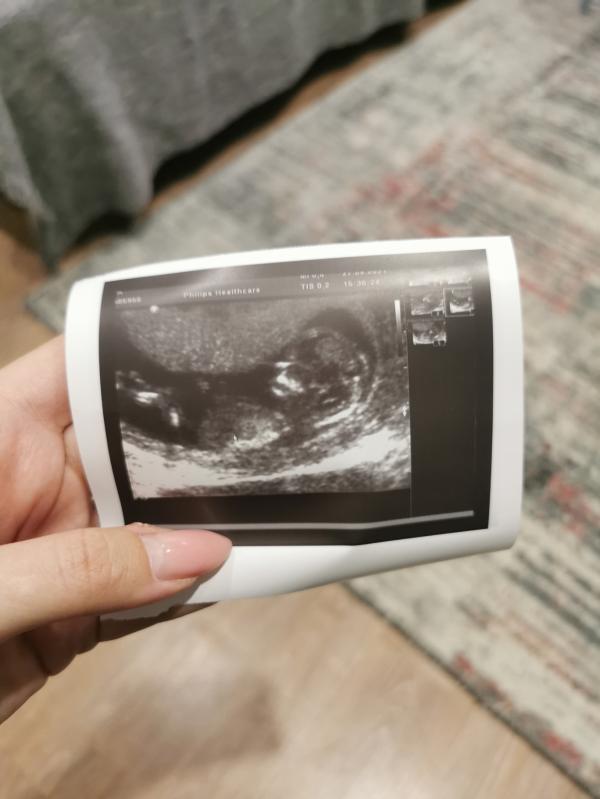

Всем привет , первый скрининг прошёл отлично 😍

Сказали , что модель у меня в животе юнная , с длинными ногами )

Пол сказали сразу , все показала , не скрывала )